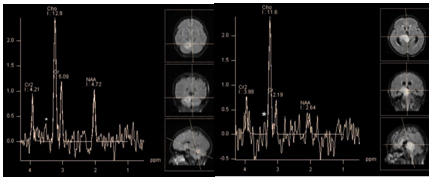

Tumefactive demyelinating lesions on conventional MRI may be indistinguishable from intra axial tumors. In this case, MR spectroscopy can provide useful information (Figure 2). Although the metabolite profiles of demyelination lesions in the acute phase and tumors may be similar, in general, tumors show higher concentrations of choline and myo-inositol. Still there is no consensus among authors.6 According to C. Majós et al. the ratio ≥ 0.9 of M-Ins/NAA and ≥ 1.9 CHO/NAA is strongly suggestive for tumors.7 According to other studies, the only reliable criterion in differentiate tumors from demyelinating lesions NAA/Cr ratio in the central areas of lesions. For demyelinating lesions average NAA / Cr ~2.4, for gliomas~0.9.8

Figure 2 Chronic tumefactive demyelinating lesion in the right Corona radiata. PRESS, TE 30 ms(a, b) PRESS, TE 30 ms, PRESS, TE 135 ms (c, d). Spectra of the lesion (a, c)in comparison with normal brain parenchyma on the opposite side (b, d). At short TE, concentrations of the main metabolites in the lesion seem normal, marked by high peaks Lac/Lip 1.3 ppm and Lip/MM 0.9 ppm. At intermediate TE lactate peak is absent, there is only a slight decrease of NAA, Cho and Cr concentrations are normal. This "benign" metabolite profile helps rule out tumor.